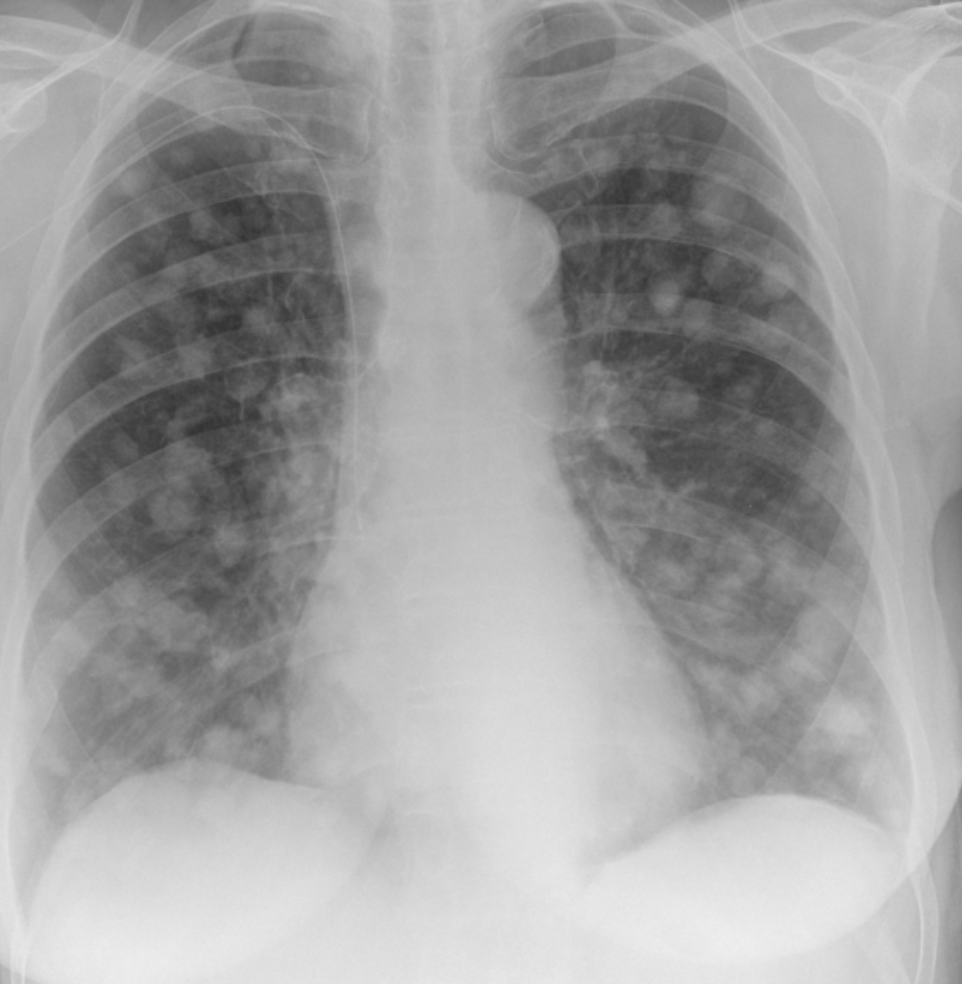

Identify this radiograph.

What are cannonball lesions or metastatic disease?